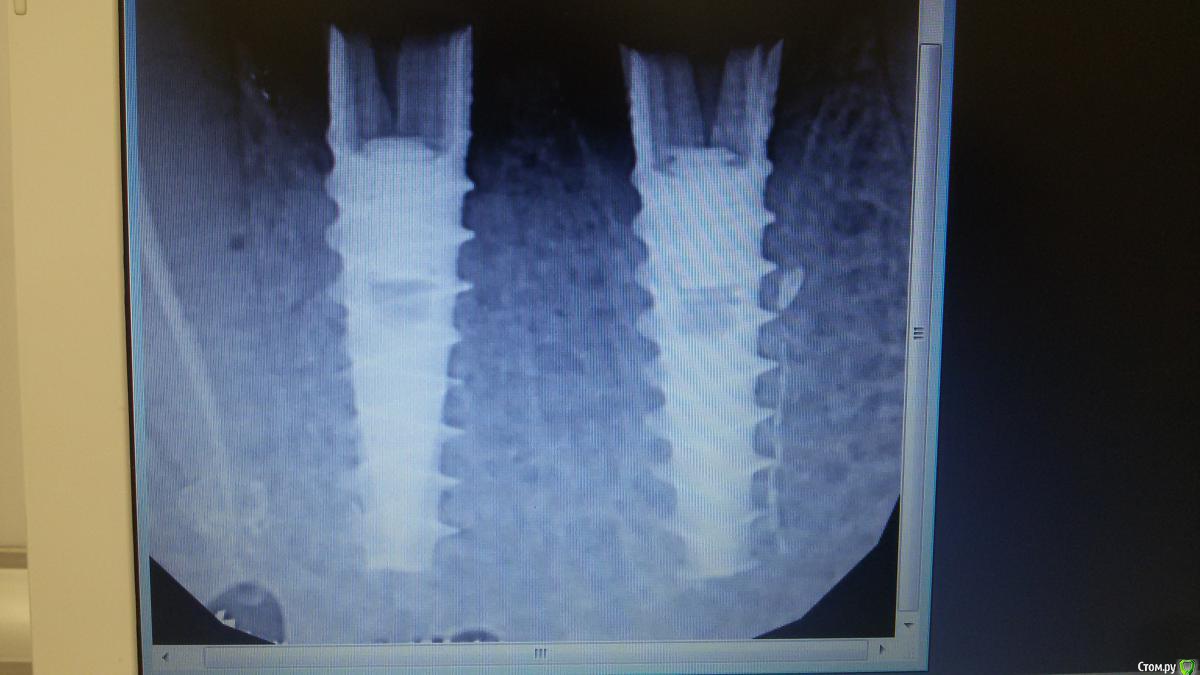

Бандерлога Опубликовано 27 сентября, 2016 Поделиться Опубликовано 27 сентября, 2016 Ранее сломанные импланты (нижние резцы) удалены: сначала пробовал Нобелвским инструментом- вроде зацепило, выкручивал рывками, но произошел перелом импланта, почувствовал как сорвался (и пациент сказал ОЙ). Оставил этот имплант в покое перешел на второй. Так же инструмент, но предворительно пропил тонким Линдеманом по бокам от импланта на 1\3 длинны - крутанул и выкрутил. Имплант который сломался пришлось Линдеманом выпиливать и расшатывать элеватором. Напрашивается вывод, что в ситуации с плотной костью и агрессивной резьбой импланта, все же перед использованием спец. инструмента пропилы делать надо. 1 Ссылка на комментарий

ДокторС Опубликовано 26 ноября, 2016 Поделиться Опубликовано 26 ноября, 2016 (изменено) А что за импланты сломаные? Обычно я беру трепан, соответствующий диаметру имплантата, пропиливаю 5-6мм, а дальше элеватор.похожи на Нико Изменено 26 ноября, 2016 пользователем ДокторС Ссылка на комментарий